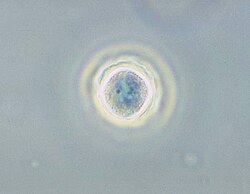

| Phase contrast micrograph of an Acanthamoeba polyphaga cyst. | |

Acanthamoeba is a genus of amoebae that are commonly recovered from soil, fresh water, and other habitats. The genus Acanthamoeba has two stages in its life cycle, the metabolically active trophozoite stage and a dormant, stress-resistant cyst stage. In nature, Acanthamoeba species are generally free-living bacterivores. However, they are also opportunistic pathogens able to cause serious and potentially fatal infections in humans and other animals.[1]